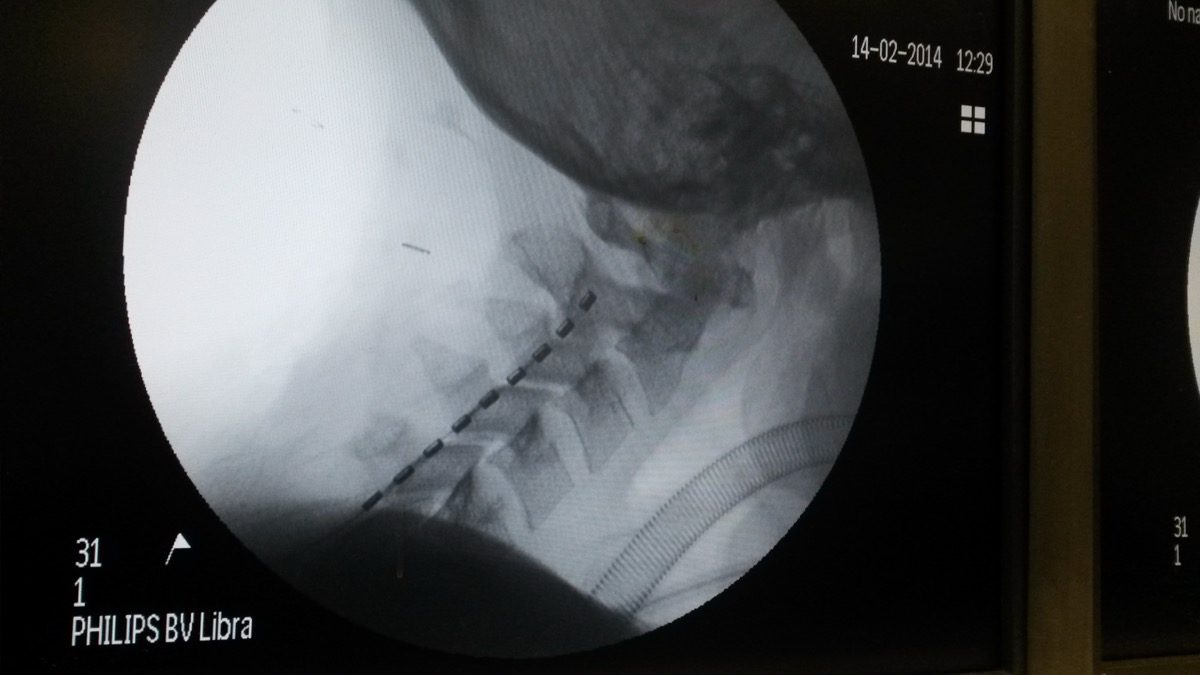

3. MRI of the spine to check for syrinx (fluid-filled cavities in the cord), tethering, or hardware complications in surgical patients